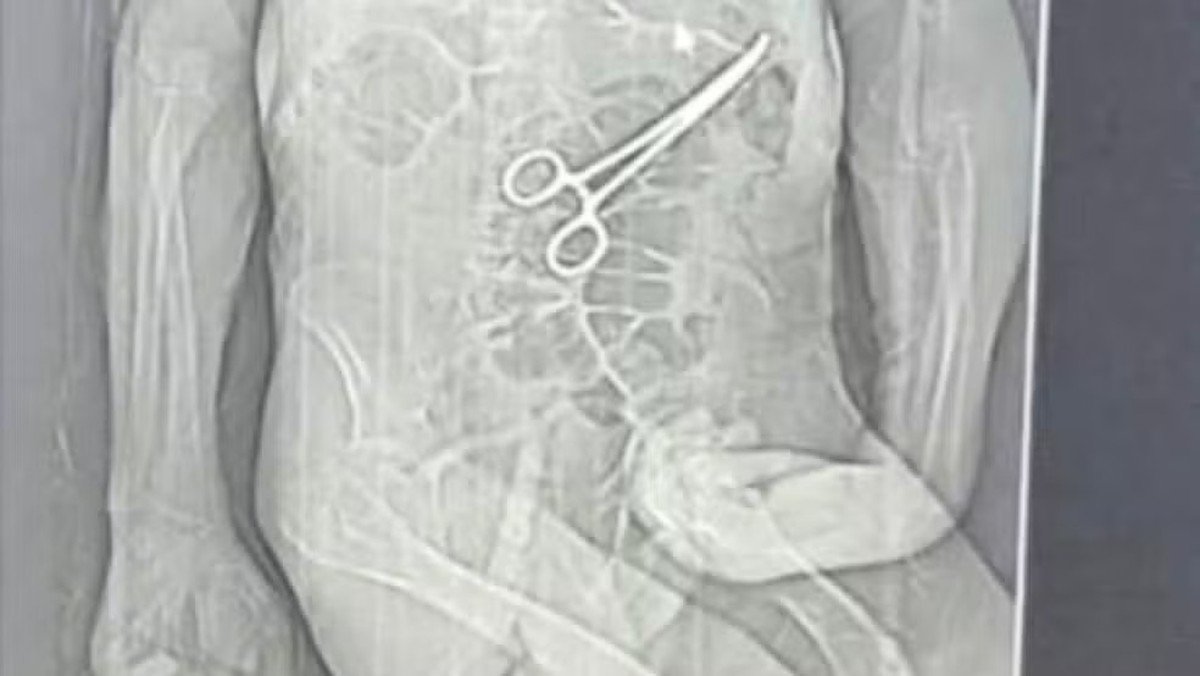

Segundo o advogado da família do idoso, as medidas legais começaram a ser adotadas depois que um exame de tomografia, divulgado por uma rádio local, chegou ao conhecimento de parentes. A imagem indicaria a presença do instrumento cirúrgico no corpo do paciente.

De acordo com a família, a pinça cirúrgica foi esquecida dentro do corpo do paciente após a primeira cirurgia, fato que, segundo os familiares, só veio à tona depois do óbito. Manoel Cardoso de Brito morreu no dia 24 de dezembro.

A Secretaria Municipal de Saúde João Pinheiro confirmou que houve a retirada de objeto durante a cirurgia do paciente e alegou que Manoel estava em estado grave, com várias comorbidades. Informou ainda que reforçou protocolos de segurança e abriu sindicância para apurar o caso.